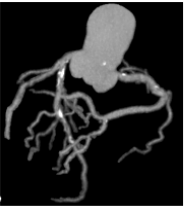

Công nghệ tim mạch Aheart

Phương pháp chỉnh sửa ECG

Hình ảnh lâm sàng